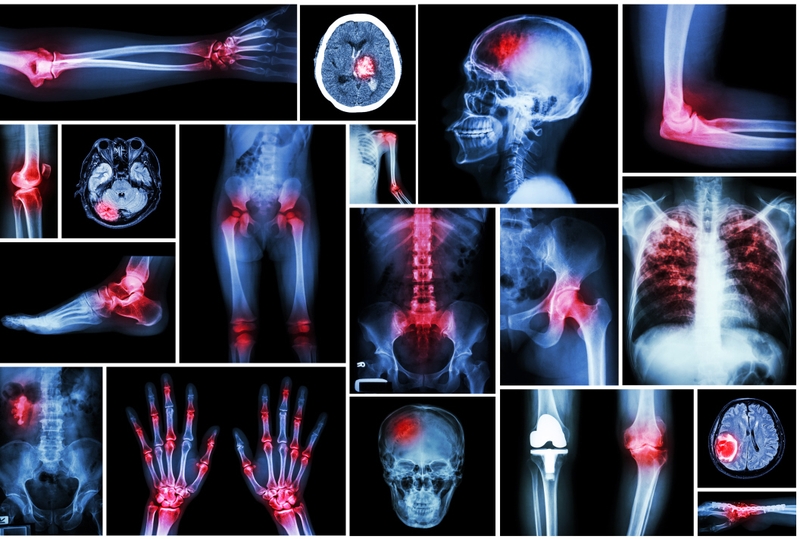

Đa chấn thương nghiêm trọng hơn chấn thương thông thường rất nhiều. Đa chấn thương là tình trạng gặp nhiều chấn thương cùng một lúc khiến sức khỏe người bệnh bị ảnh hưởng nghiêm trọng. Vậy đa chấn thương nguy hiểm thế nào và xử trí ra sao?

Đa chấn thương là tình trạng có ít nhất 2 tổn thương nghiêm trọng ở nhiều vùng hoặc ở nhiều cơ quan khác nhau trên cơ thể. Đa chấn thương thường là những chấn thương có độ nghiêm trọng cao, gây mất rất nhiều máu. Đa chấn thương cũng dẫn đến nhiều rối loạn như rối loạn hô hấp, rối loạn tuần hoàn,…

Đa chấn thương có thể bao gồm tổn thương não bộ, bụng, cột sống, các chi, xương chậu và các cơ quan, bộ phận khác trên cơ thể. Tuy nhiên, các thống kê cho thấy tỷ lệ tổn thương thường gặp nhất thường là: